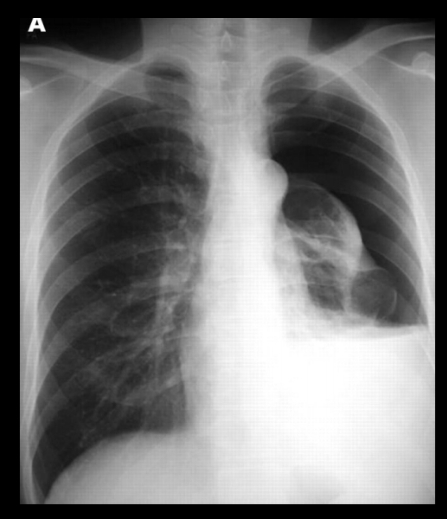

Qué se ve en un neumotórax en Rx. y TC?

• Hiperclaridad

• Pérdida de trama vascular

• pulmón colapsado